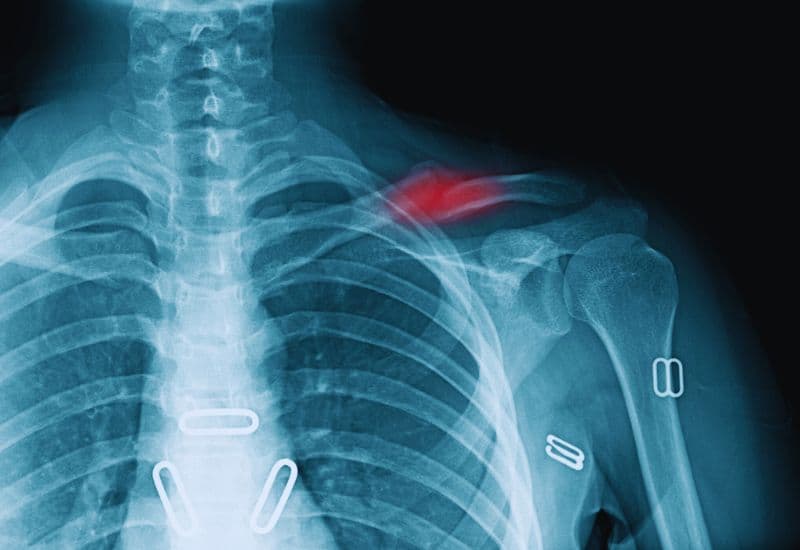

Gãy xương quai xanh ở đoạn giữa